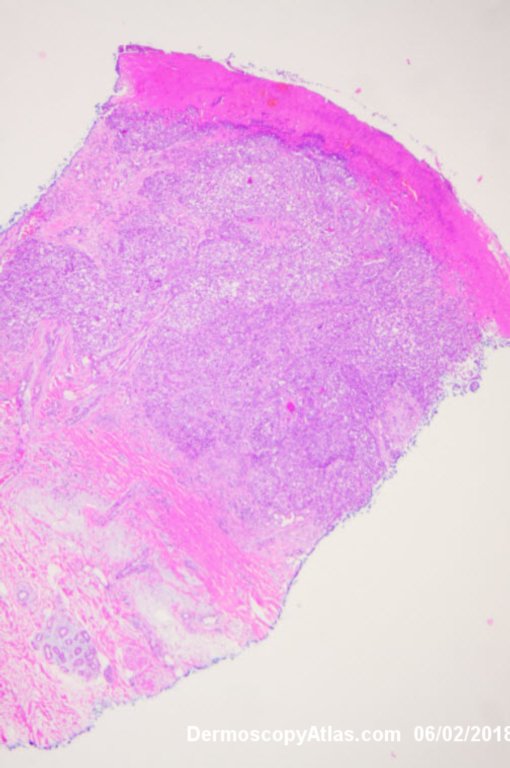

Site: Leg

Diagnosis: Melanoma invasive

Lady in her early 80s who presented with this lesion on her ankle. The pigmented area had been there for some time but the pink area was bleeding and new. Shave of surrounding area and a punch biopsy of the new pink area showed mainly surrounding in situ melanoma with invasive melanoma in the pink area 1.8 mm thick. Having a 2cms margin excision of the whole area and a graft.